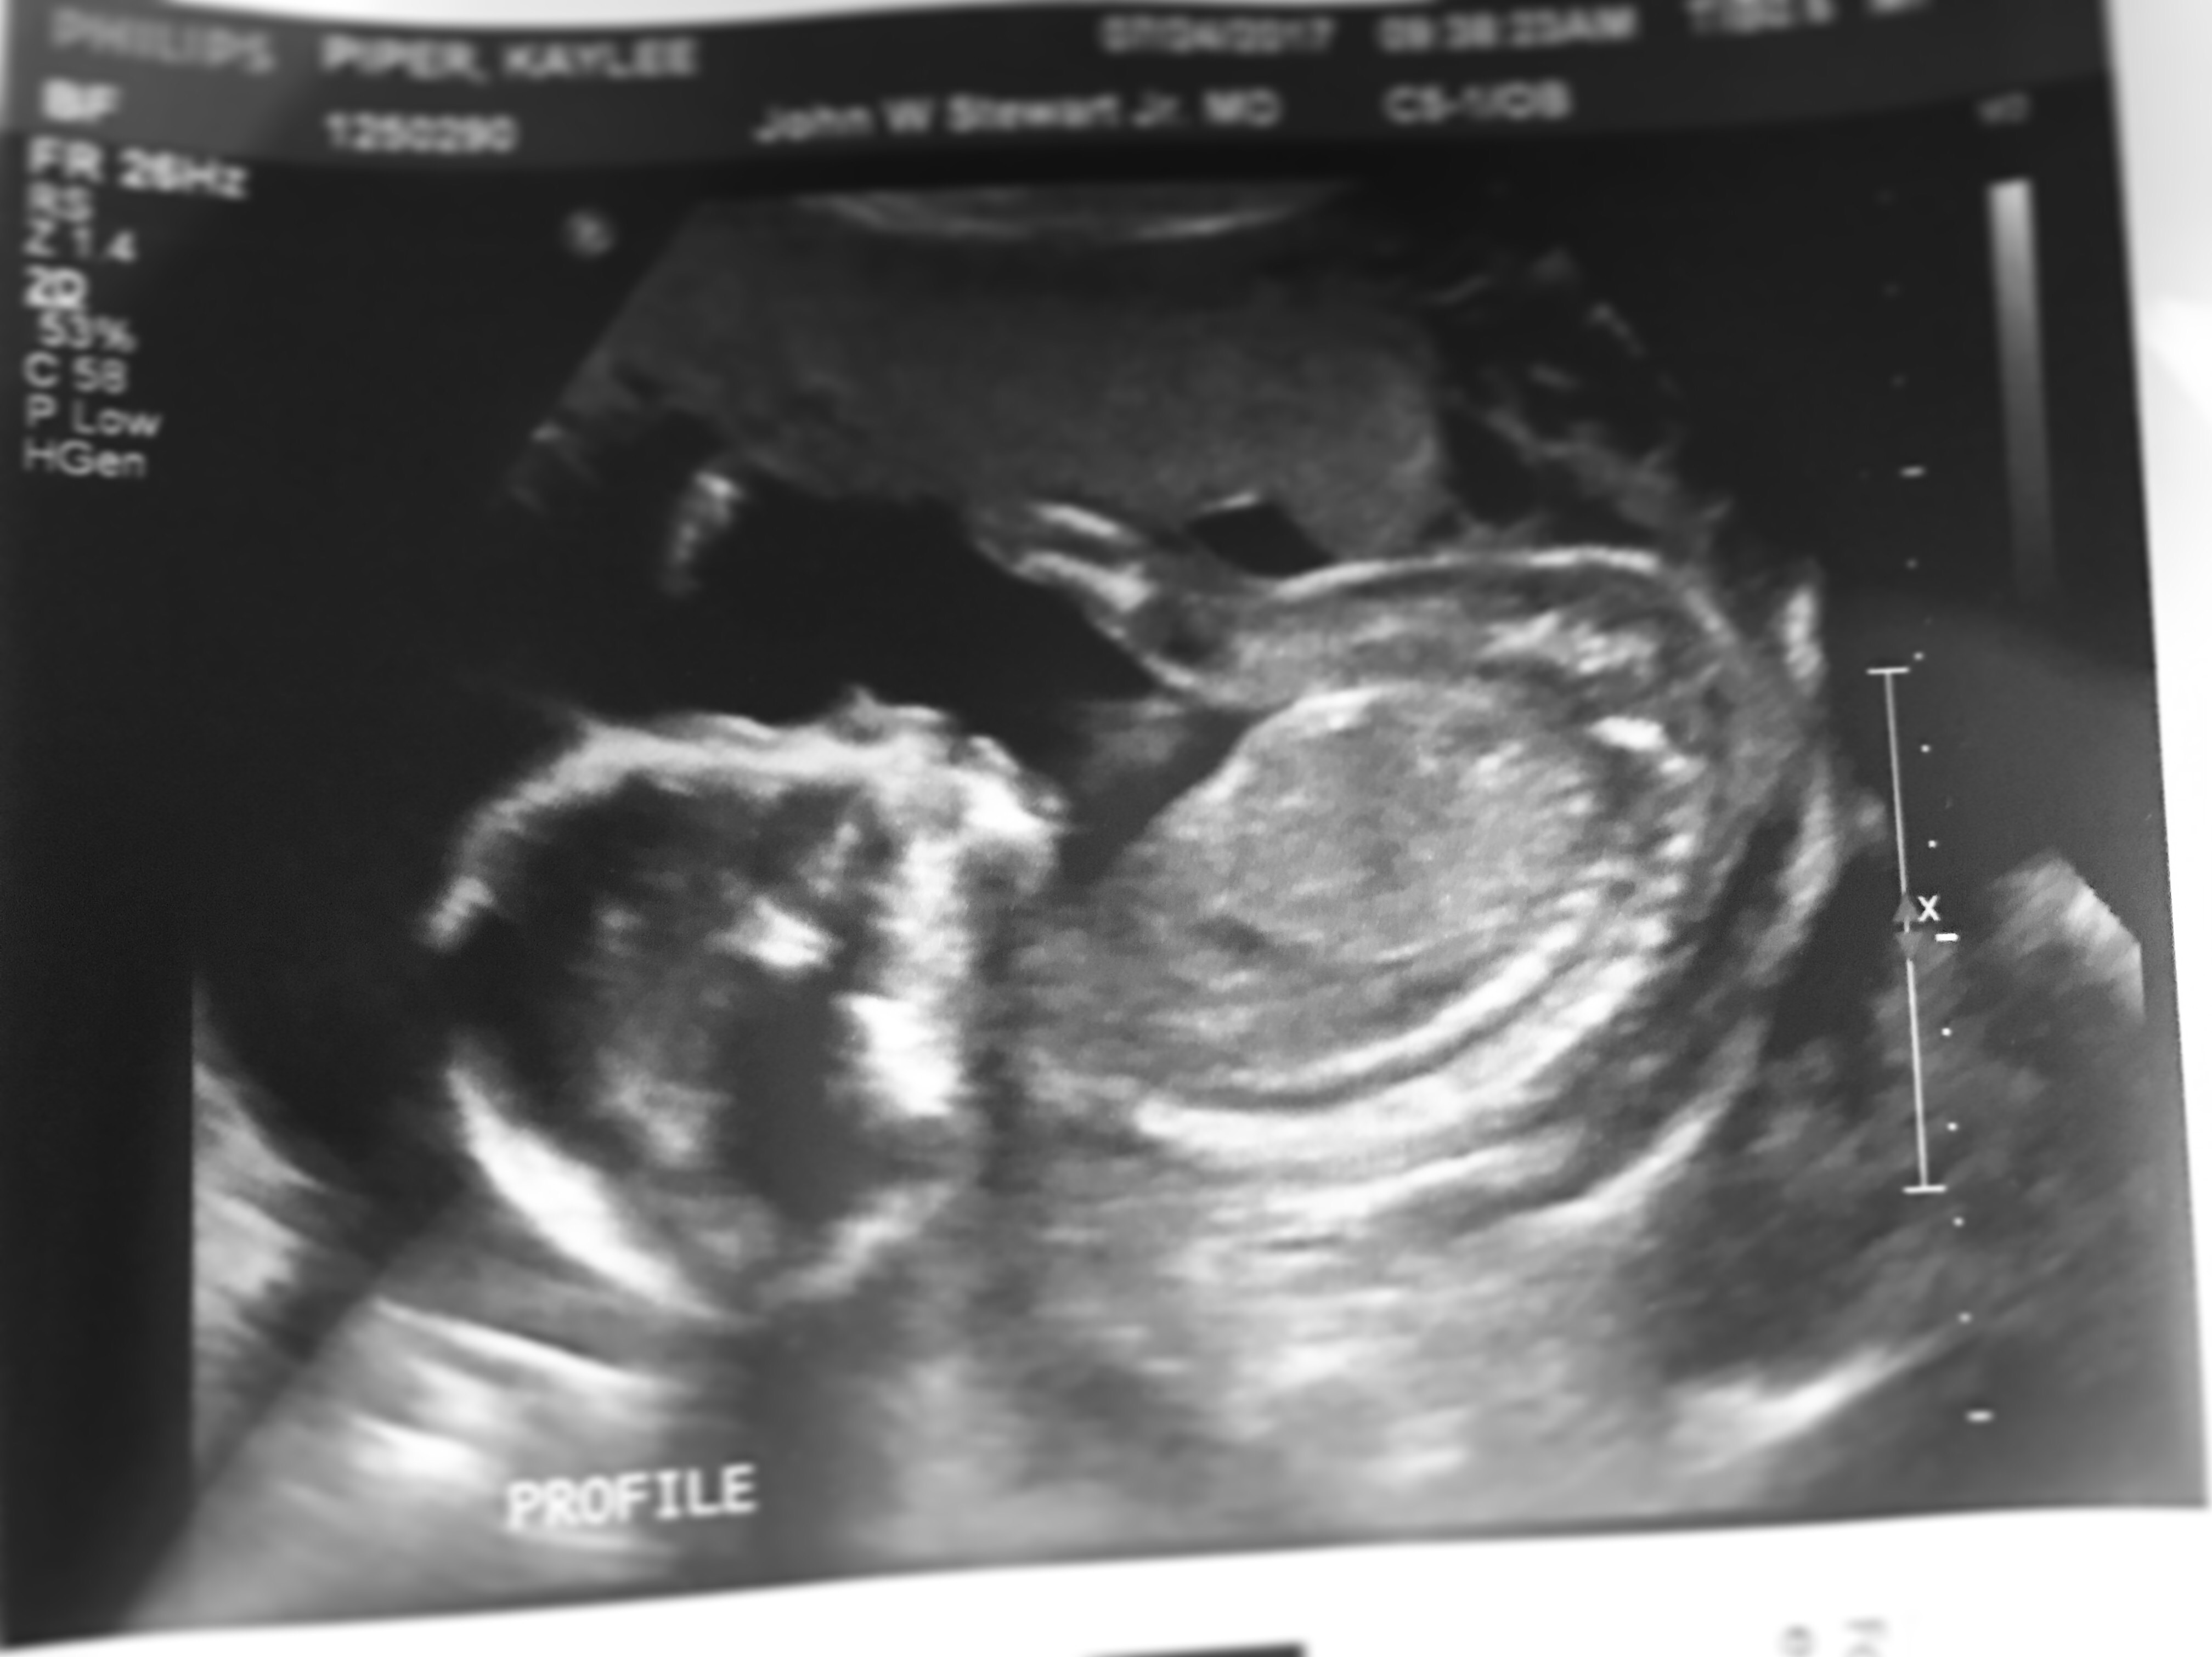

Last week, on July 24th, I celebrated my 28th birthday. I was also exactly 20 weeks pregnant (halfway there!) and we had the anatomy scan of our little baby. It was the best birthday I could ask for because the Doctor had confirmed that everything (baby and me) were perfectly healthy and progressing nicely. Before Brian and I entered the Doctor’s office, we secretly wrote our guess of the sex on a piece of paper and put it in an envelope to open once we got back in the car to see what each other thought. I have been VERY neutral this whole time about boy vs girl. We had a named picked out for a girl and noticed daily that I had little “signs” or reminders of either that name or something related to it. I would say 90% of our families thought girl, even my Chiropractor had voted girl. For me, especially since it’s our first child, I didn’t have any preference. One day while walking around Target, I was in the baby clothing section cooing over newborn girl swimsuits. They are so tiny and cute – my favorite was a watermelon print with ruffles! I then walked over to the boys section to browse the little the socks and shoes – there I had a moment. I would describe as a “cold chill” and a feeling I can’t put into words. I paused and smiled to myself. There I had a strong feeling we were having a boy. About two minutes into our anatomy scan we had our answer, the little flutters I had been feeling in my belly was a BOY!